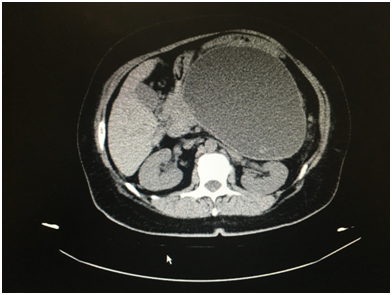

A female of 45 years old presented to emergency room for intense abdominal pain the last 8 hours that did not diminished with analgesic consumption. She had pathological background of acute biliary pancreatitis 8 weeks ago, and underwent laparoscopic cholecystectomy 2 days after resolution of this. Patient refers that the last two weeks she noticed postpandrial fulfill and a mild epigastric pain, constant and no related with any factor that she could identify. The last two days the abdominal pain increase without irradiation and she began with throwing after food intake. At physical exam she had dehydrated tissues and mucous membranes, with adequate ventilation, 24 breathings per minute secondary to pain, abdomen with distention in epigastrium and with a palpable mass at this level of about 12 centimeters in diameter, it can be mobilized partially and increase the pain at palpation. The rest of the physical exam was normal. A CT scan was requested, and reported a collection in the front wall of the pancreas of 160x80x73mm and a volume of 430cc, with a thick wall (6mm) and heterogeneous hypo-echogenic content (Figures 1-3). A pancreatic pseudocyst was diagnosed and a laparoscopic approach was decided according to our previous experience in the development of this technique and the good results. A transgastric approach was performed with previous opening of the anterior gastric wall (Figure 4) (Figure 5), drainage of 500cc of pancreatic liquid, and an anastomosis performance between pseudocyst anterior wall and gastric posterior wall with prolene 00 with a continuous stitch (Figure 6), and posterior close of the anterior gastric wall with another continuous stich of the same suture (Figure 7). Total bleeding was estimated in 20cc and surgical time was 120 minutes, 40 minutes less than our first case. Only four trocar ports were used, 2 of 5mm (epigastric and in right hypochondrium) and 2 of 12 mm (umbilical and left hypochondrium). Patient began feeding after 48 hours and was discharged at 72 hours uneventfully. At four months follow up she still asymptomatic.

Figure 1 Abdominal CT scan, axial view showing the pancreatic pseudocyst and gastric compression.